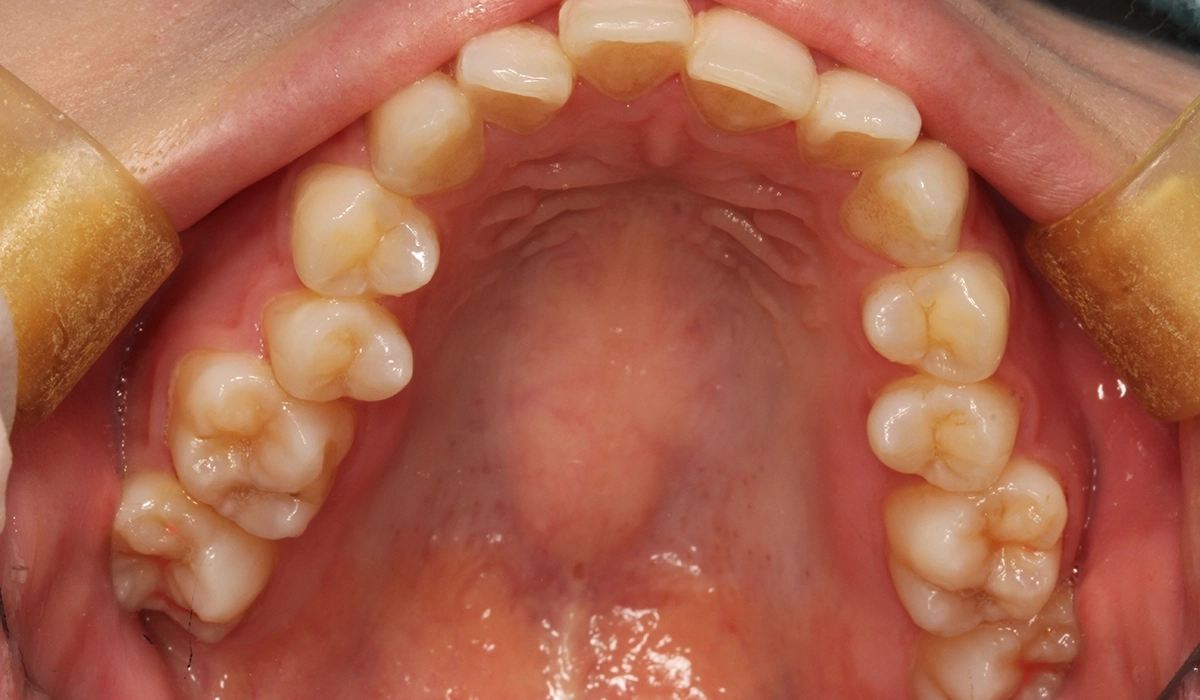

術前:上顎

術後:上顎